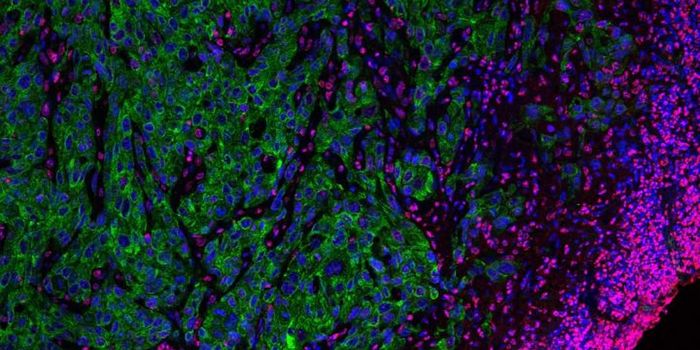

MAR 18, 2021Drug Discovery & DevelopmentResearchers have developed a prototype for a new kind of cancer immunotherapy. The therapy uses engineered T-cells to ta ...